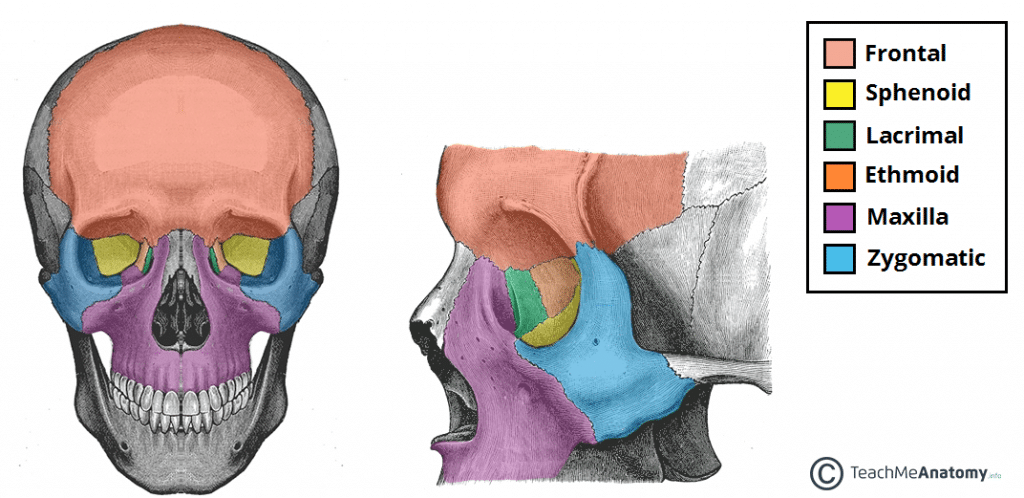

The orbit can be thought of as a pyramidal structure, with the apex pointing posteriorly and the base situated anteriorly. The boundaries of the orbit are formed by seven bones.

• Roof (superior wall) – Formed by the frontal bone and the lesser wing of the sphenoid. The frontal bone separates the orbit from the anterior cranial fossa.

• Floor (inferior wall) – Formed by the maxilla, palatine and zygomatic bones. The maxilla separates the orbit from the underlying maxillary sinus.

• Medial wall – Formed by the ethmoid, maxilla, lacrimal and sphenoid bones. The ethmoid bone separates the orbit from the ethmoid sinus.

• Lateral wall – Formed by the zygomatic bone and greater wing of the sphenoid.

Fig 1

The anterior and lateral views of the bony orbit.